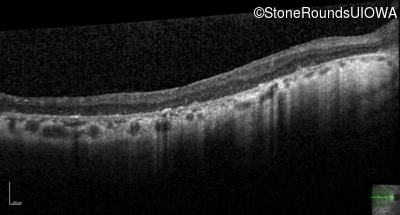

Optical Coherence Tomography - Right - 20/100 +1

Exemplar / OCT Stack

Optical Coherence Tomography - Left - 20/70